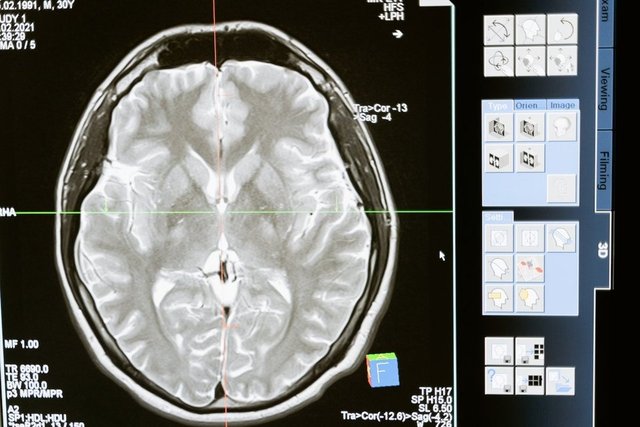

2006 yılında çekilen beyin tomogrofileri, Price'ın beynindeki iki düzineden fazla alanın normalden daha büyük olduğunu ortaya çıkardı. Bunun ne anlama geldiği hâlâ ucu açık bir sorudur.

Fotoğraf temsilidir